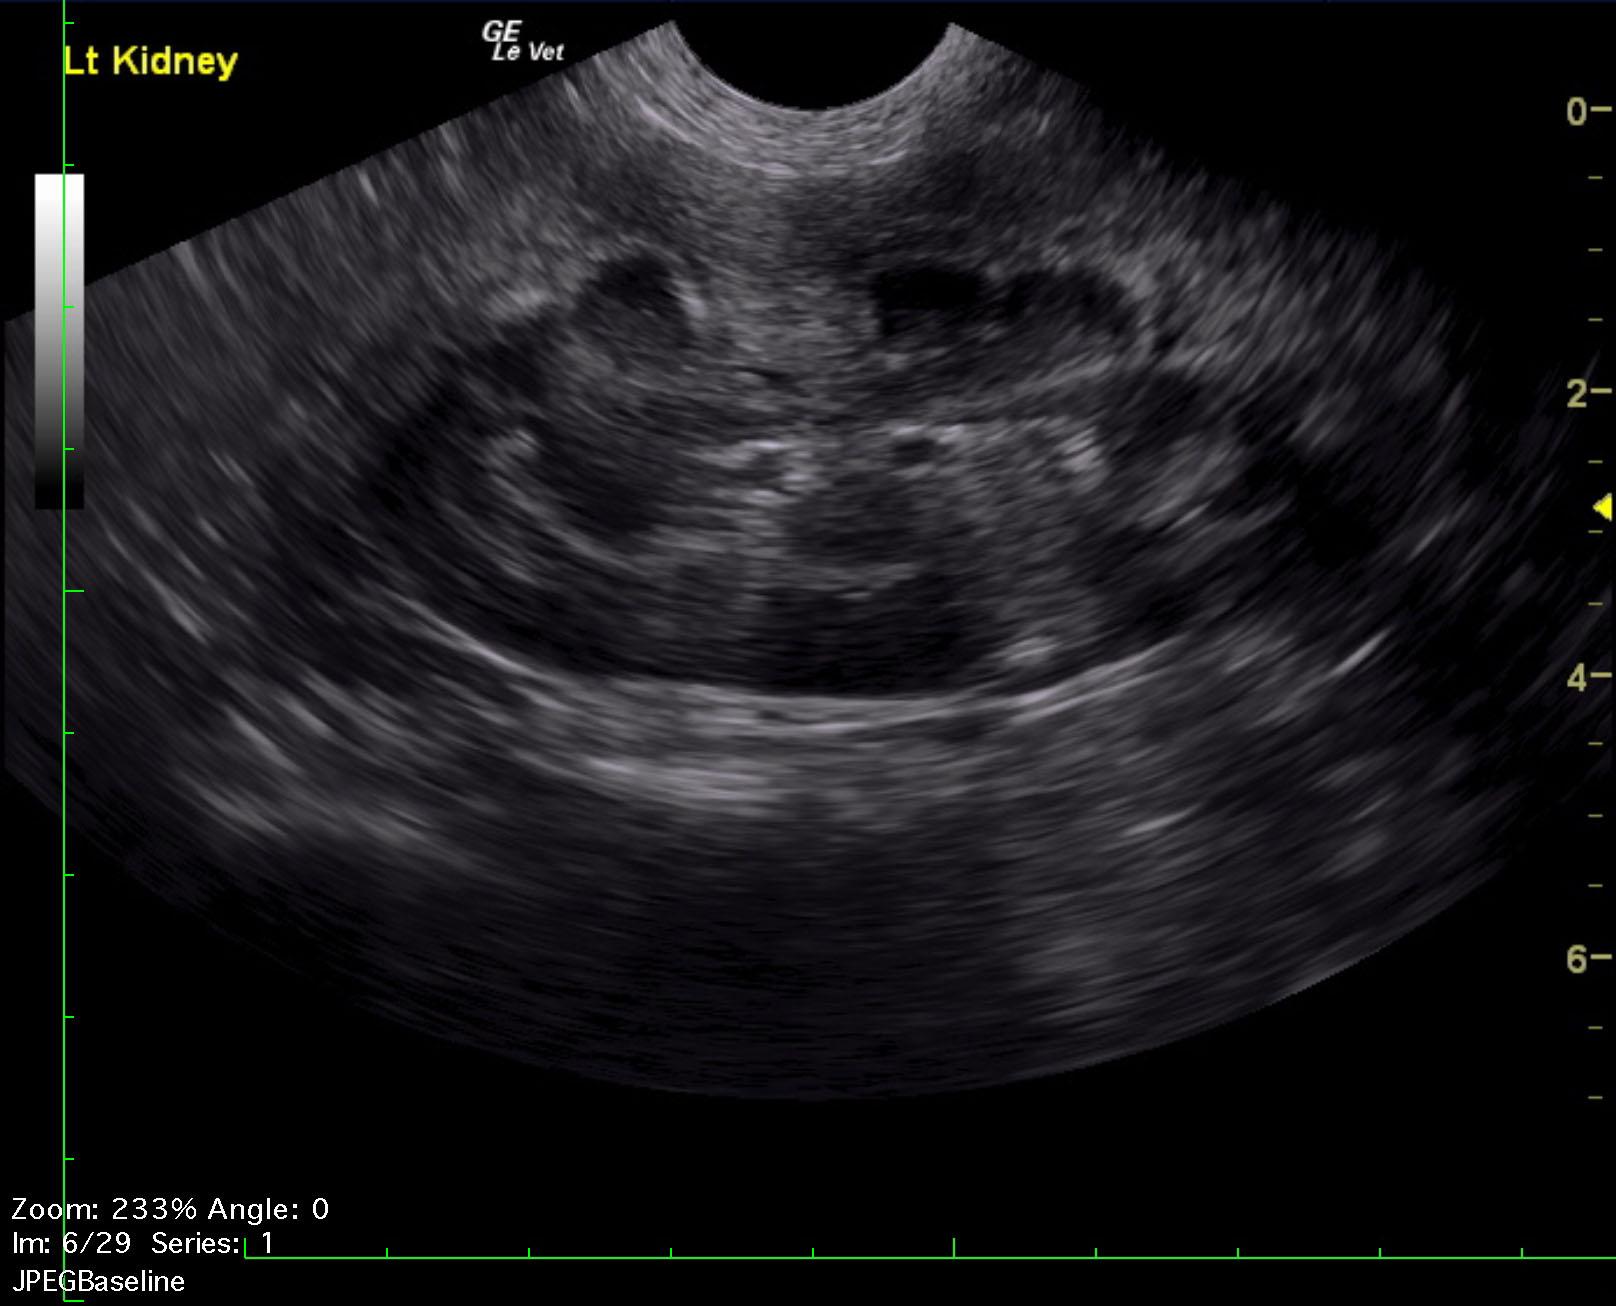

A 1-year-old NM German shepherd with a history of PU/PD and hypercalcemia was presented for evaluation of lethargy, weight loss, and anorexia. Left-sided nephromegaly was present on survey radiographs. Abnormalities on serum biochemistry were hypercalcemia, azotemia, and mildly elevated ALT activity.